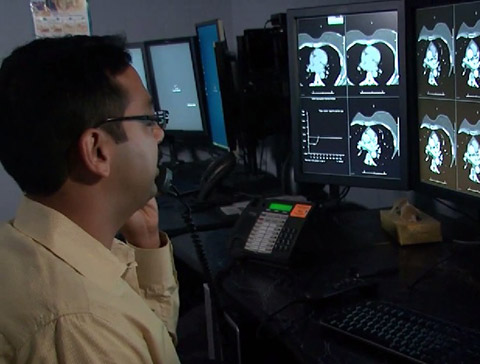

"باستخدام تقنيات التصوير المتقدمة من Philips مثل التصوير ثلاثي الأبعاد وعرض الشدة القصوى (MIP) وإعادة التشكيل متعدد الأسطح (MPR)، يمكننا الحصول على الصور بسهولة ومعالجتها لتحسين تشخيصنا. نحن نأخذ فكرة أفضل عن المستوى الذي وصل إليه المرض، كما يمكننا تقديم نصائح أفضل إلى الطبيب السريري حول ما يحدث." دكتور دارسي ليتل